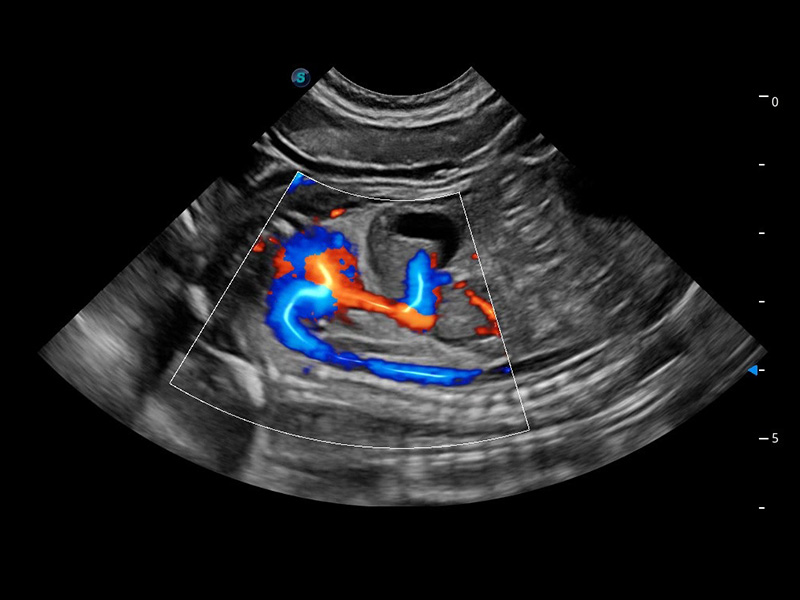

ProPet 60 作为一款高端台式动物超声设备,为动物医生的日常诊断提供了一系列贴合动物临床需求、解决临床实际问题的高级成像功能。凭借全系列高清探头,满足医生对腹部、心脏、生殖、浅表、肌骨等成像的所有需求,切实帮助您提升检查效率,提高诊断信心。

ProPet 60 尊享版

兽用彩色多普勒超声诊断系统